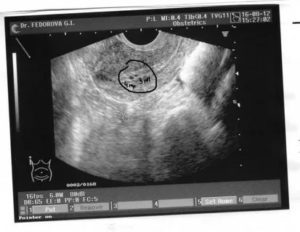

УЗИ на 5 неделе беременности не слишком информативно, поэтому даже опытный специалист, который работает на хорошем оборудовании, не сможет много сказать помимо того, что вы будете мамой. При увеличении изображения в несколько раз он сможет определить желточный мешок и сам эмбрион.

УЗИ на 5 неделе беременности позволяет увидеть сам эмбрион, который пока очень похож на небольшой цилинд. Его длина — пять миллиметров, а вес всего 3.5 грамма. Однако несмотря на то, что он еще совсем мал, внутри него происходят важнейшие процессы, определяющие все последующее развитие.

УЗИ 5 недель беременности показывает весьма схематично, поэтому вряд ли вас порадует полосатый фон с непонятными точками в вашем семейном альбоме. У вас будет еще достаточно времени и возможностей, чтобы запечатлеть кроху.